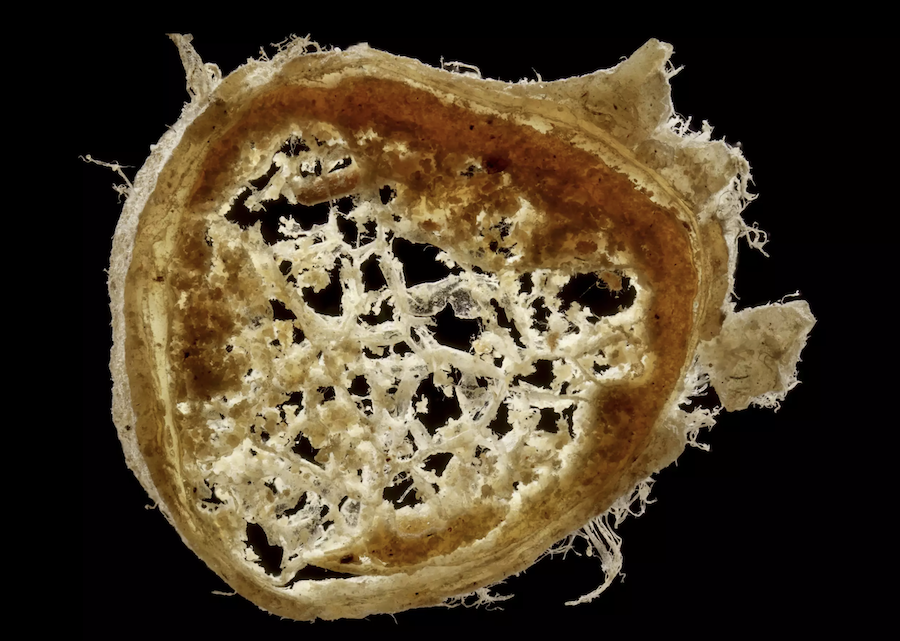

Colour of the iris of the eye. Anatomy of the optic nerve. Explanation of the conduction of the sensations of sight. Method of examining the cerebral substance. Comments about English criticisms of his observations of the brain. Figure of the transverse section of an optic nerve of a cow is was attached to the letter.